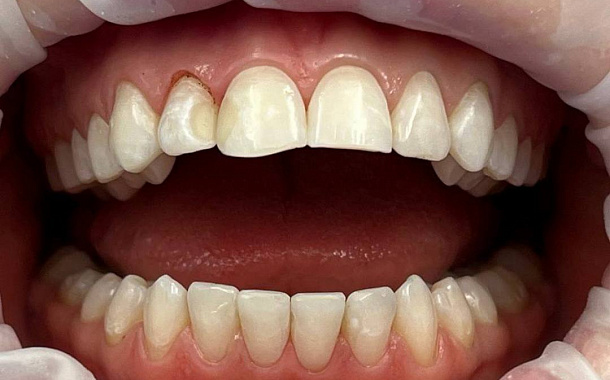

Полный прайс-листКейсы: до и после